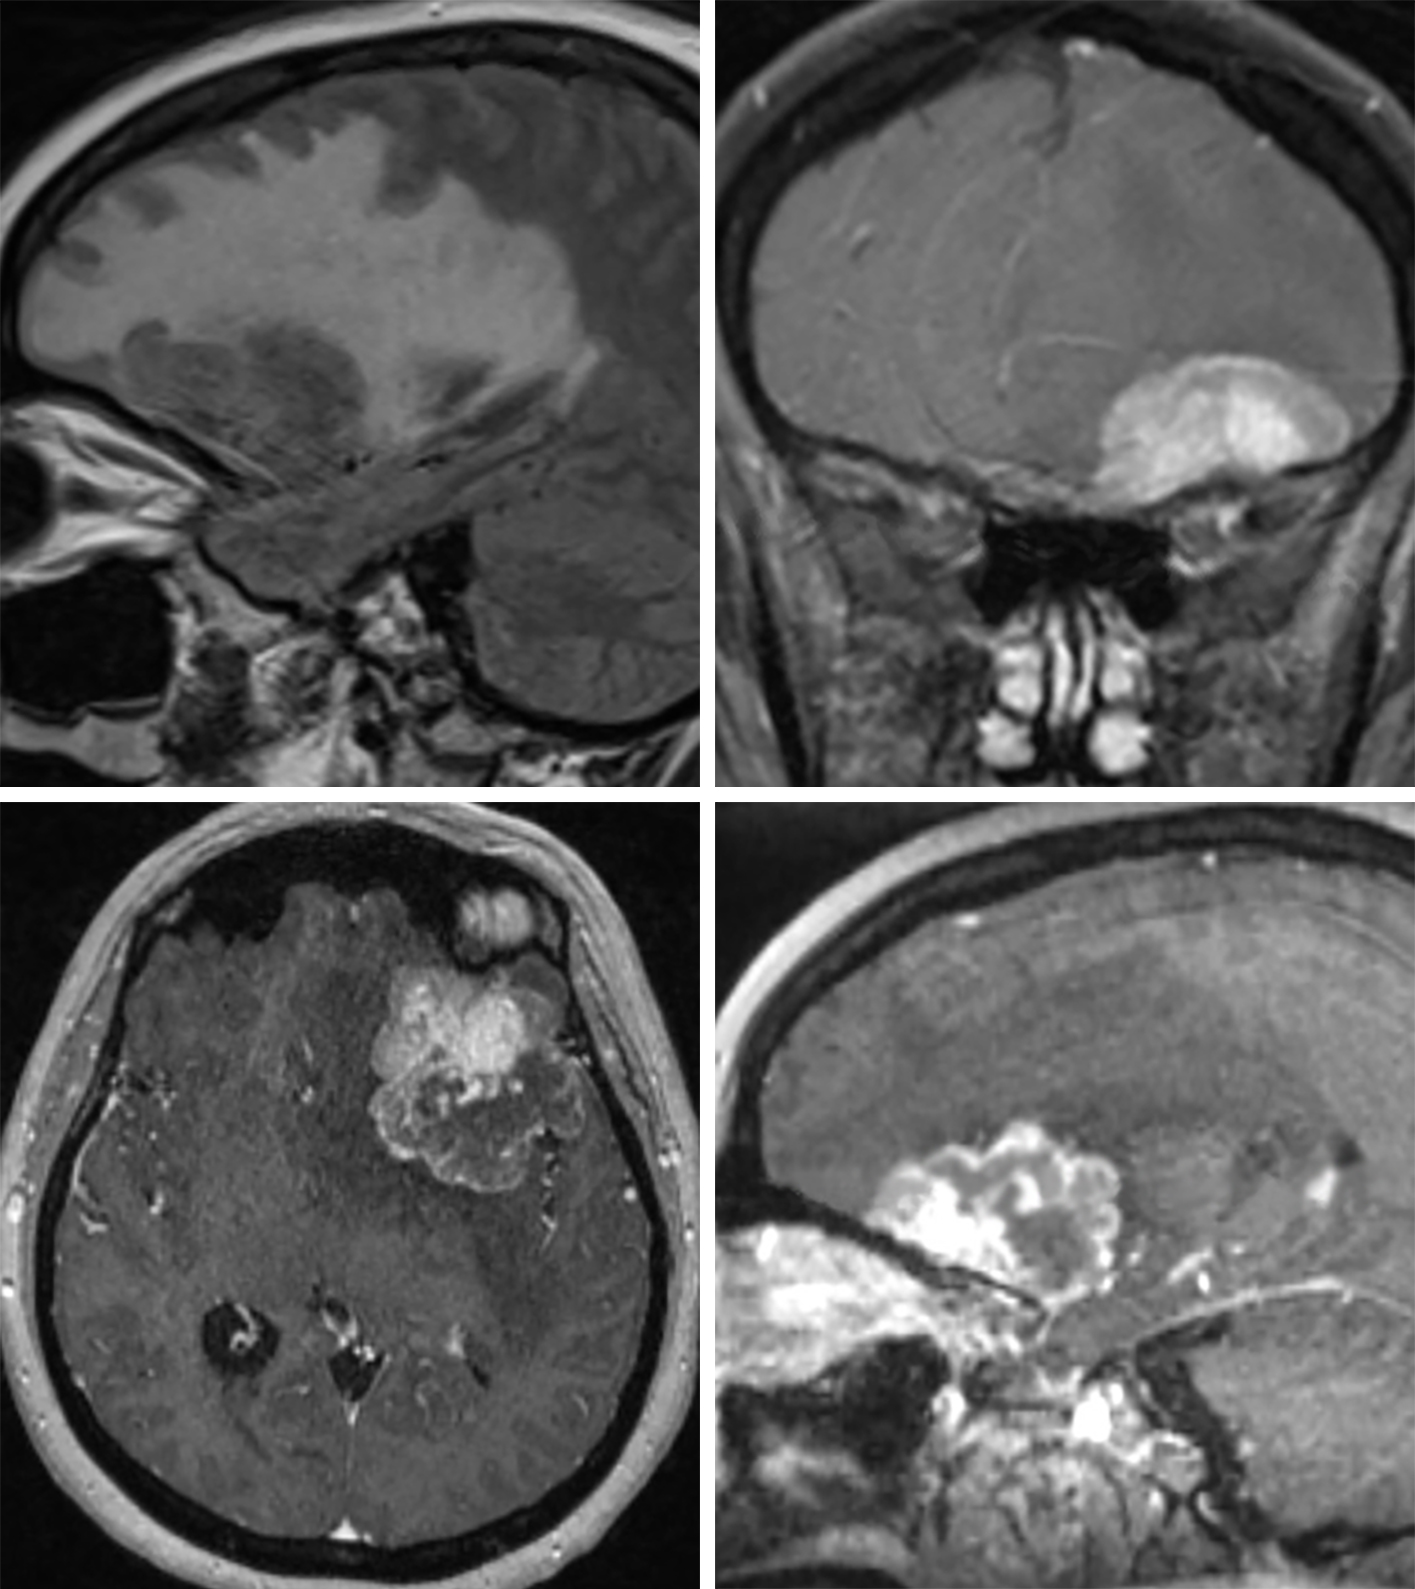

Metastasis | Cohen Collection | Volumes | The Neurosurgical Atlas